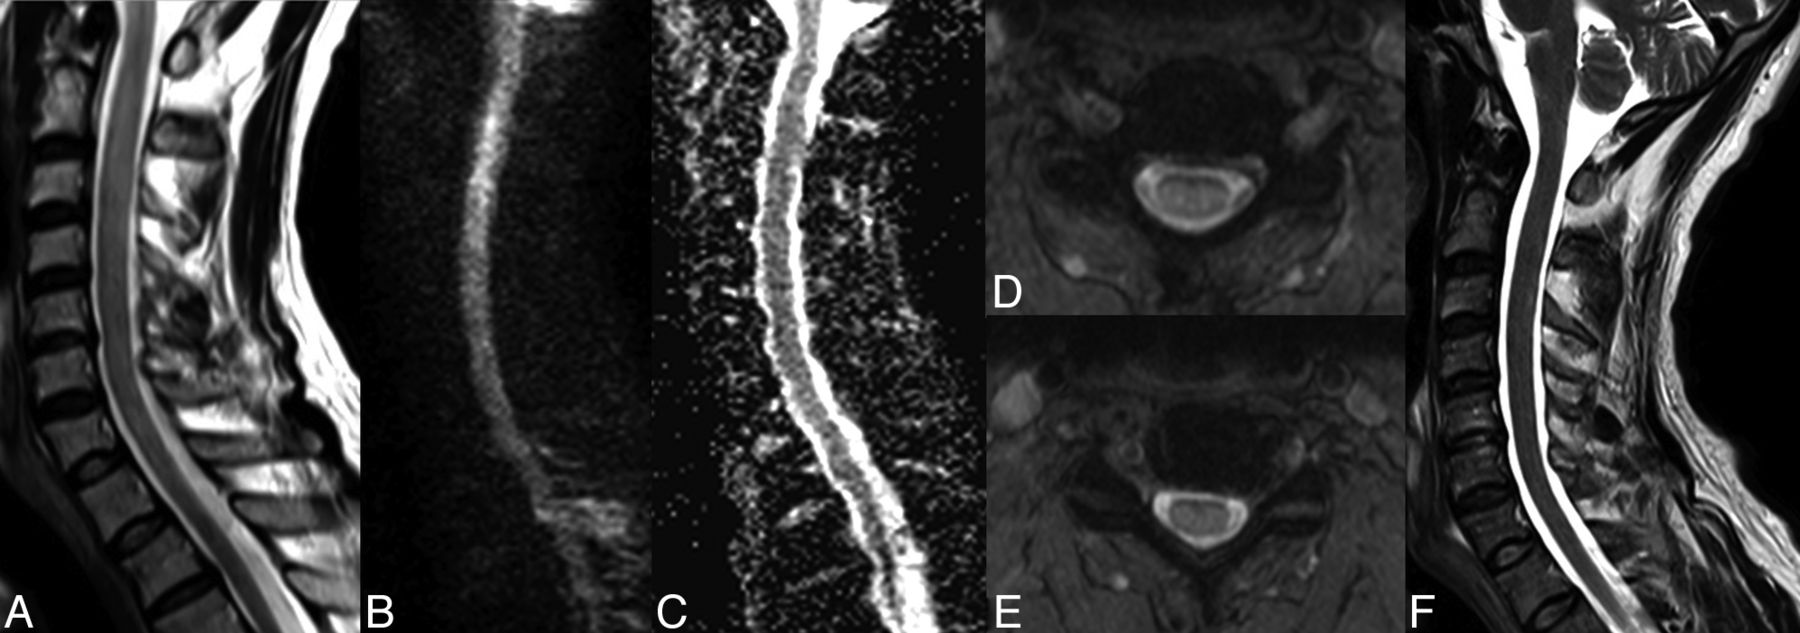

Reversible cervical spinal cord lesion due to decompression sickness. MR imaging shows an extensive lesion causing enlargement of the cervical spinal cord. The lesion appears as a high signal on sagittal (A) and axial T2WI (D and E) and on DWI (B) without concomitant signal decrease on the ADC map (C). All these characteristics, with complete healing without a scar as shown on sagittal T2WI (F) obtained 2 weeks later, are consistent with vasogenic edema (referred to as an “ischemic-like” lesion in the On-line Table).

On the other hand, various radiologic and histopathologic findings have been published to support the venous infarction theory. First, the more frequent occurrence of lateral and posterior column white matter lesions compared with gray matter lesions in spinal cord decompression sickness is more likely a consequence of an obstruction of the slow-flowing epidural venous bed by nitrogen bubbles, which leads to vasogenic edema (Figs 1 and 2).5,8 In some cases, there may be additional venous infarction (Fig 3B, -C). Similar lesions have been provoked experimentally in dogs.9 Second, several histopathologic studies have demonstrated venous obstruction and white matter congestion.45,46 Third, vasogenic edema, appearing as high signal on both DWI and ADC maps, was observed by Vollmann et al in 201147 in a case of spinal cord decompression sickness, also suggesting a venous rather than arterial pathologic process.